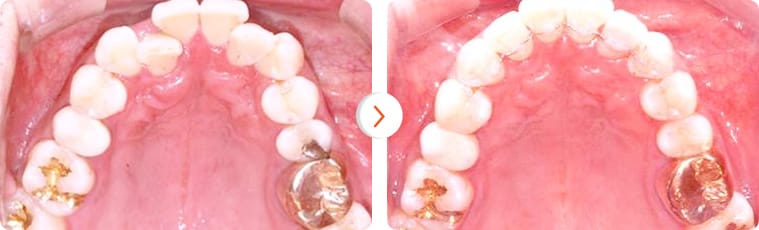

“Khách hàng nam 30 tuổi chỉnh hình răng sử dụng minivis sau 15 tháng”

Trường hợp lệch khớp cắn nhẹ. Bệnh nhân nữ 25 tuổi – Thời gian điều trị: 8 tháng